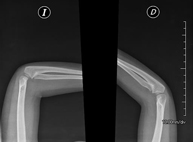

- RX Extremitats

Tècnica que usa els raigs X a través de la qual s'obtenen imatges de l'interior de les extremitats per al seu estudi, especialment dels ossos. Indicacions: traumatisme, infeccions articulars. - RX Artrografia